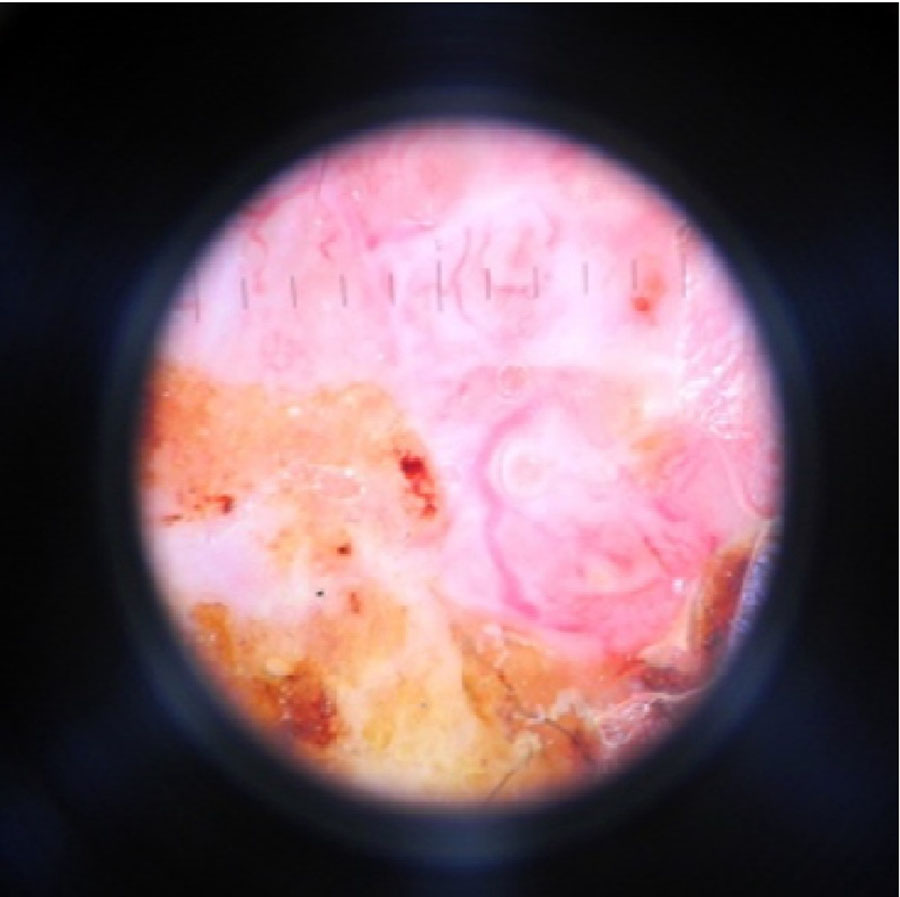

The diagnostic dermoscopy corresponds to basal-cell carcinoma (multiple atypical blood vessels are visible) and squamous cell carcinoma (hairpin and linearblood vessels, whitish ring-shaped areas are visible) (Figure 5).

Figure 5. Dermatoscopic picture of basal cell skin cancer in patient C. (Heine Delta 20, eyepiece-10, immersion, non-polarized mode)